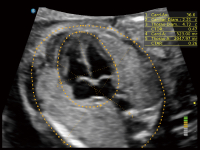

丰富的血流动力学检测技术,可在不同医疗场景中高效捕捉血流信号,助力临床诊疗。

在传统血流的基础上优化扫查和算法策略,能够更好的抑制组织信息,提炼红细胞运动信息,得到更高帧频,高灵敏度和分辨率的血流信号,还原更真实的血流动力学。